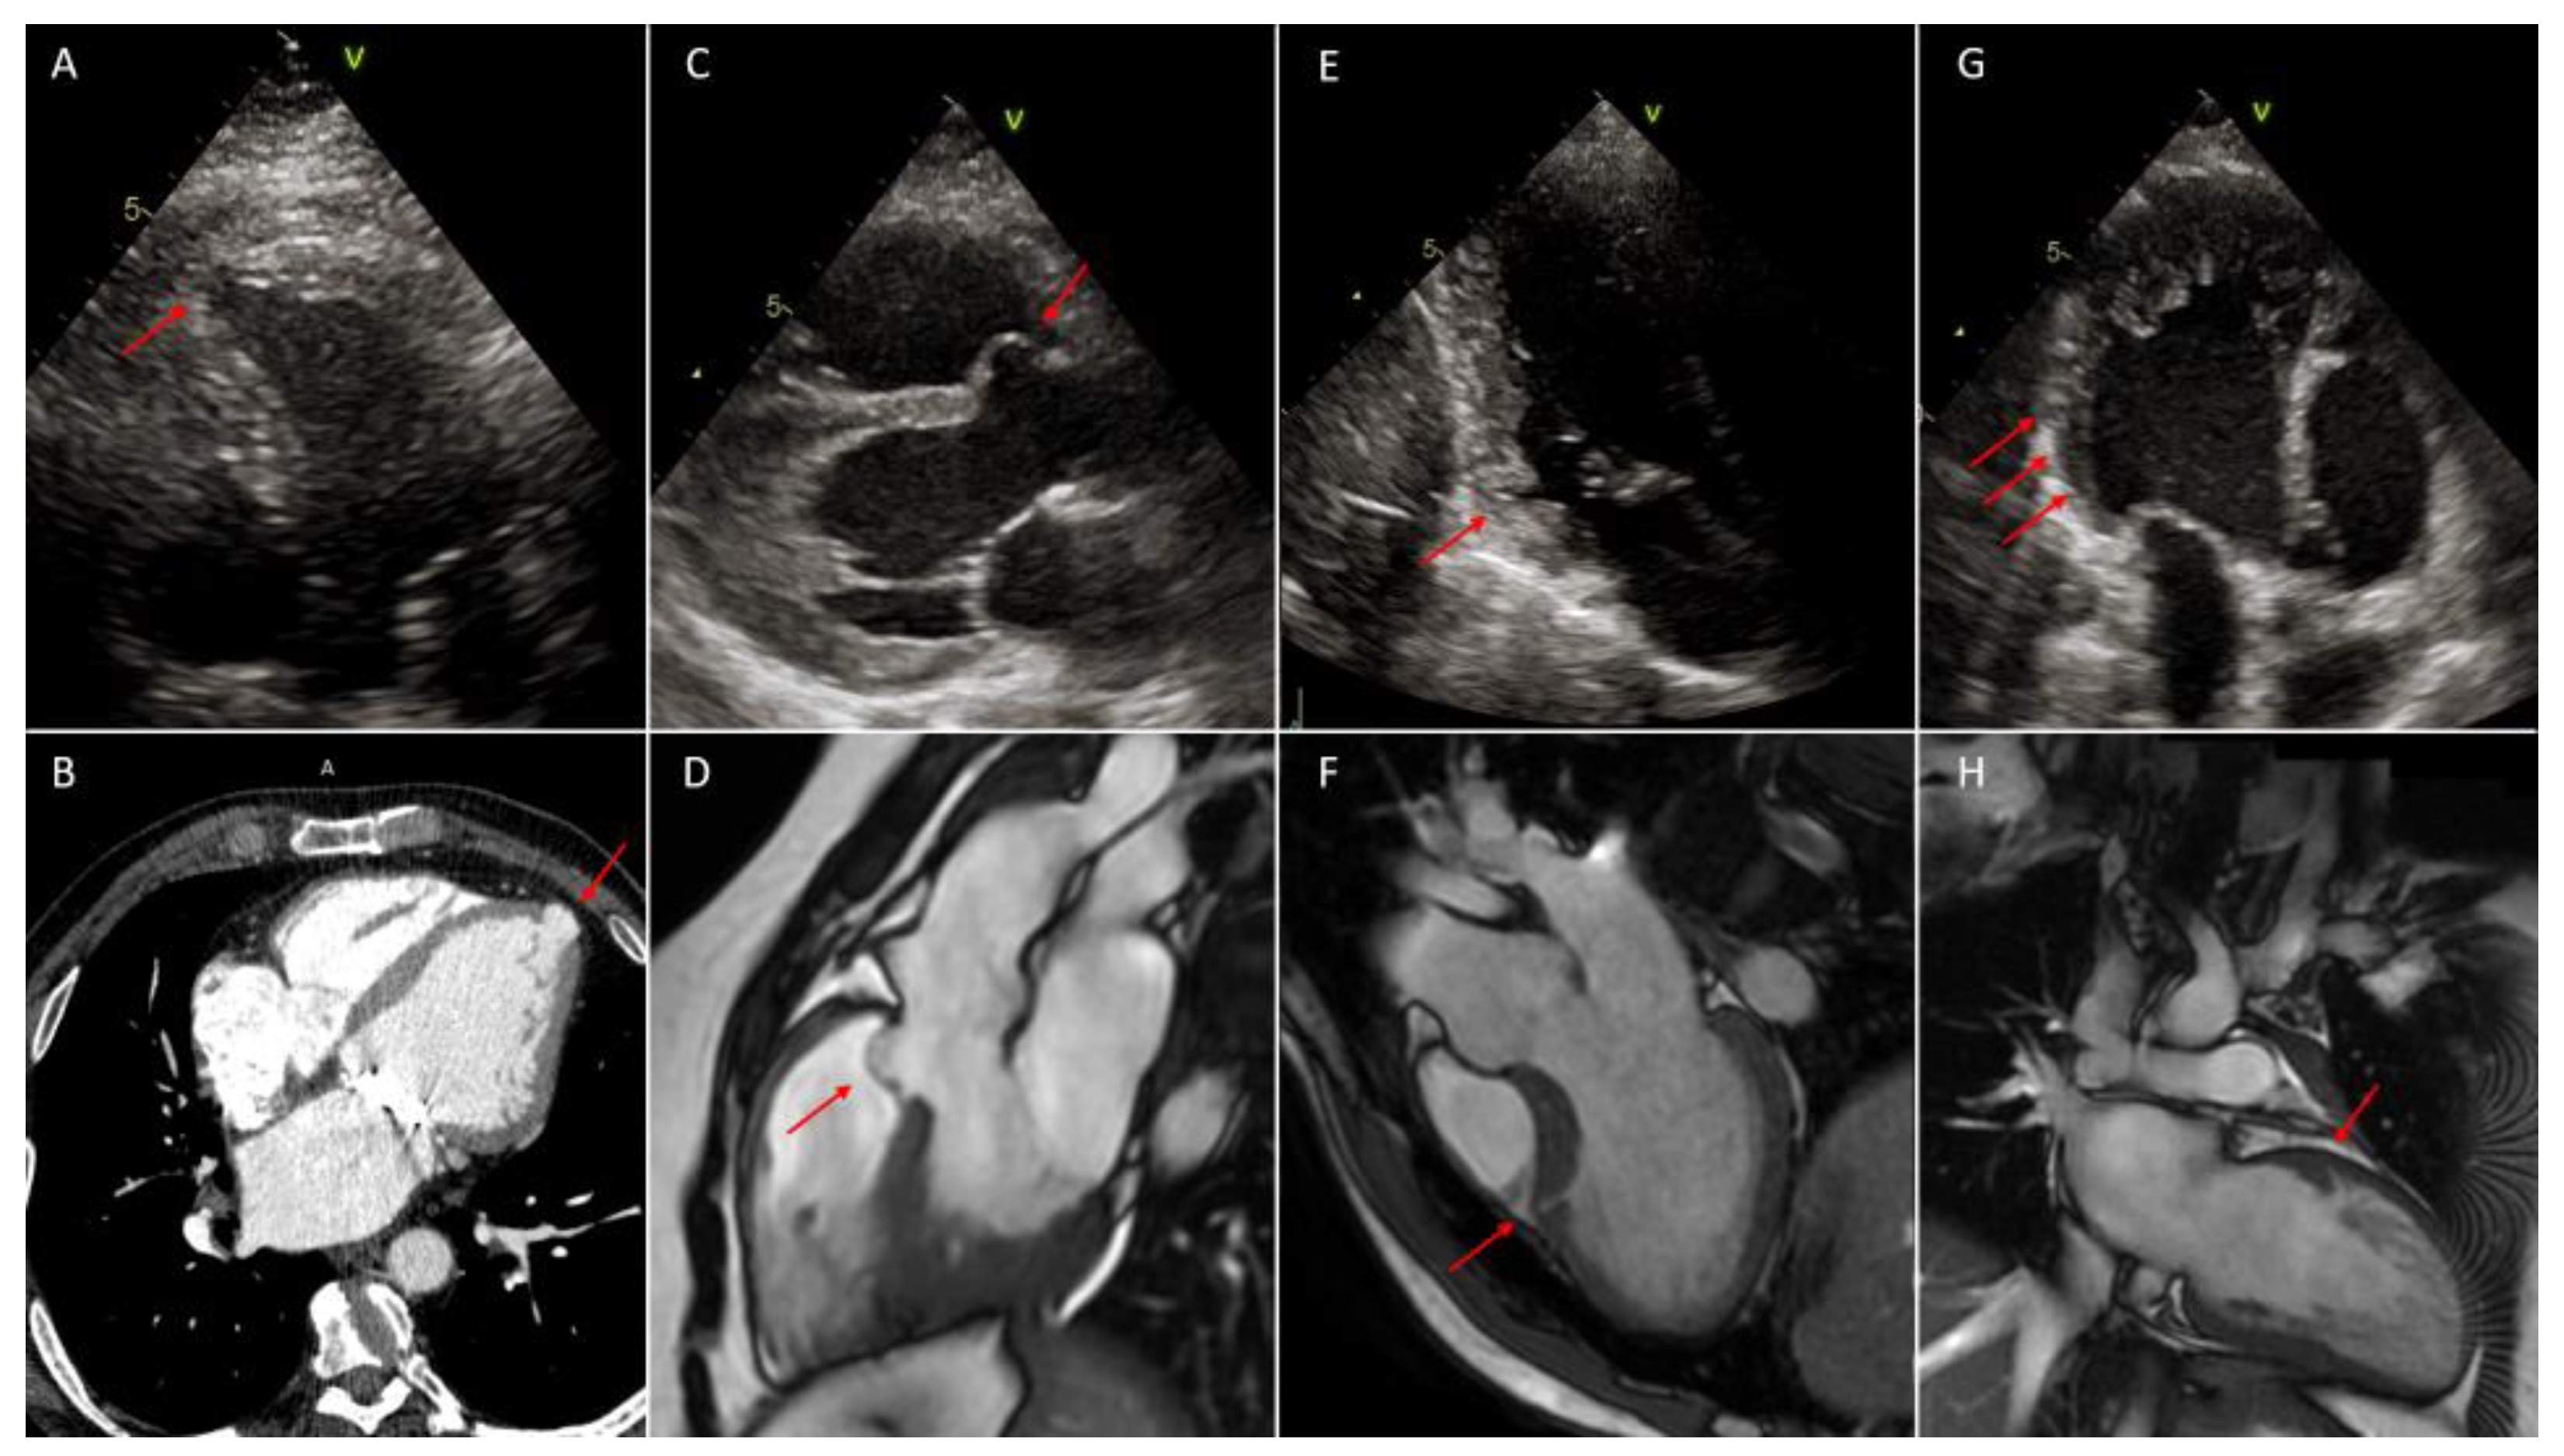

Figure 3.

In all figures red arrows indicate the lesion. (A): left ventricular apical diverticulum, 2D-Multimodality imaging of outpouchings/invaginations. Echocardiography in apical four chambers view; (B): left ventricular apical diverticulum, cardiac contrast-enhanced computer tomography (CCT); (C): left ventricular congenital septal aneurysm in left ventricular non-compaction (LVNC), 2D-echocardiography in parasternal long axis (PLAX) view; (D): left ventricular congenital septal aneurysm, cardiac magnetic resonance (CMR); (E): inferior basal myocardial crypt; 2D-echocardiography in apical two chambers view; (F): myocardial crypt of the mid antero-septal wall in hypertrophic phenotype of basal septum, CMR; (G): multiple myocardial recesses in (LVNC), 2D-echocardiography in apical parasternal long axis (APLAX) view; (H): myocardial recess in left ventricular non-compaction (LVNC), CMR.